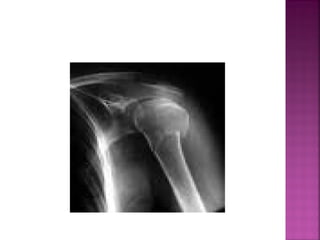

◦ Pérdida completa y estable de la congruencia

de las superficies óseas que forman una

articulación.

Signos y síntomas :

•Dolor intenso en el área

del hombro.

•Deformidad visible.

•Cabeza del humero

palpable.

•Incapacidad para mover el

brazo o tocar la oreja del

lado opuesto.

Signos y síntomas: •Dolor intenso en el área del hombro. •Deformidad visible. •Cabeza del humero palpable. •Incapacidad para mover el brazo o tocar la oreja del lado opuesto.